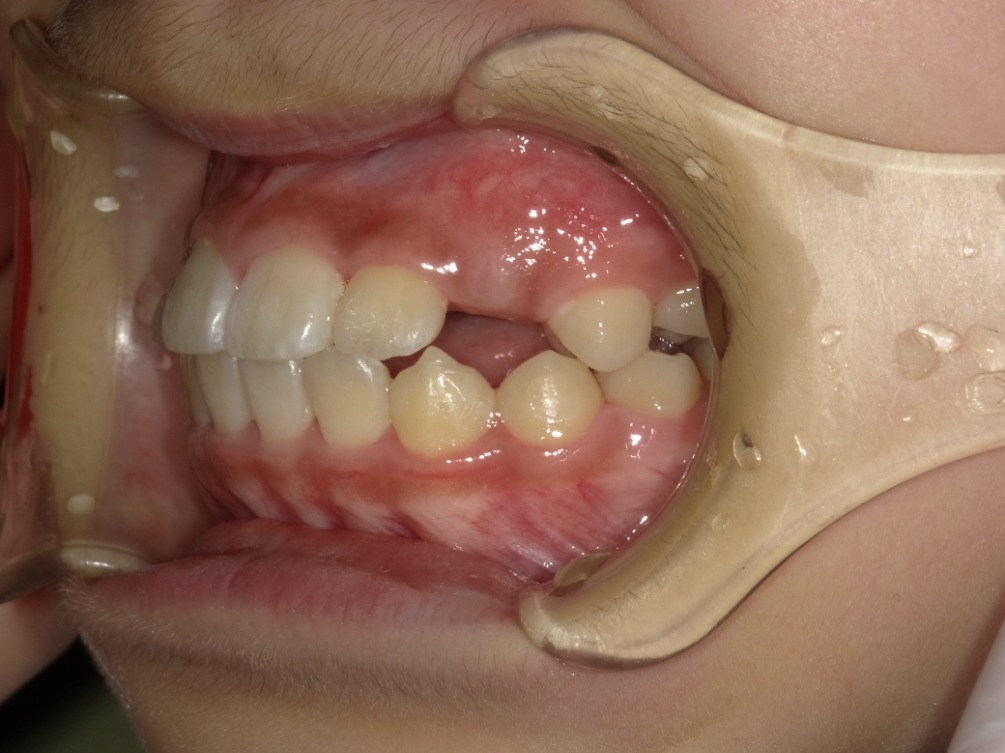

• BEFORE

症例集 インビザライン 左横

AFTER

スペース不足を整えるために、歯の表面にアタッチメント(白い突起)をつけ、IPR(歯と歯の間を削る)を行いました。

スペース不足を放置していた場合、叢生と言って歯が重なって生えてくる可能性の高い状態でした。

そのため、治療開始時には右下の前から3番目の永久歯の生えるスペースがありませんでした。

矯正治療を行うことで、スペースができ、治療後には正しい位置に生えています。